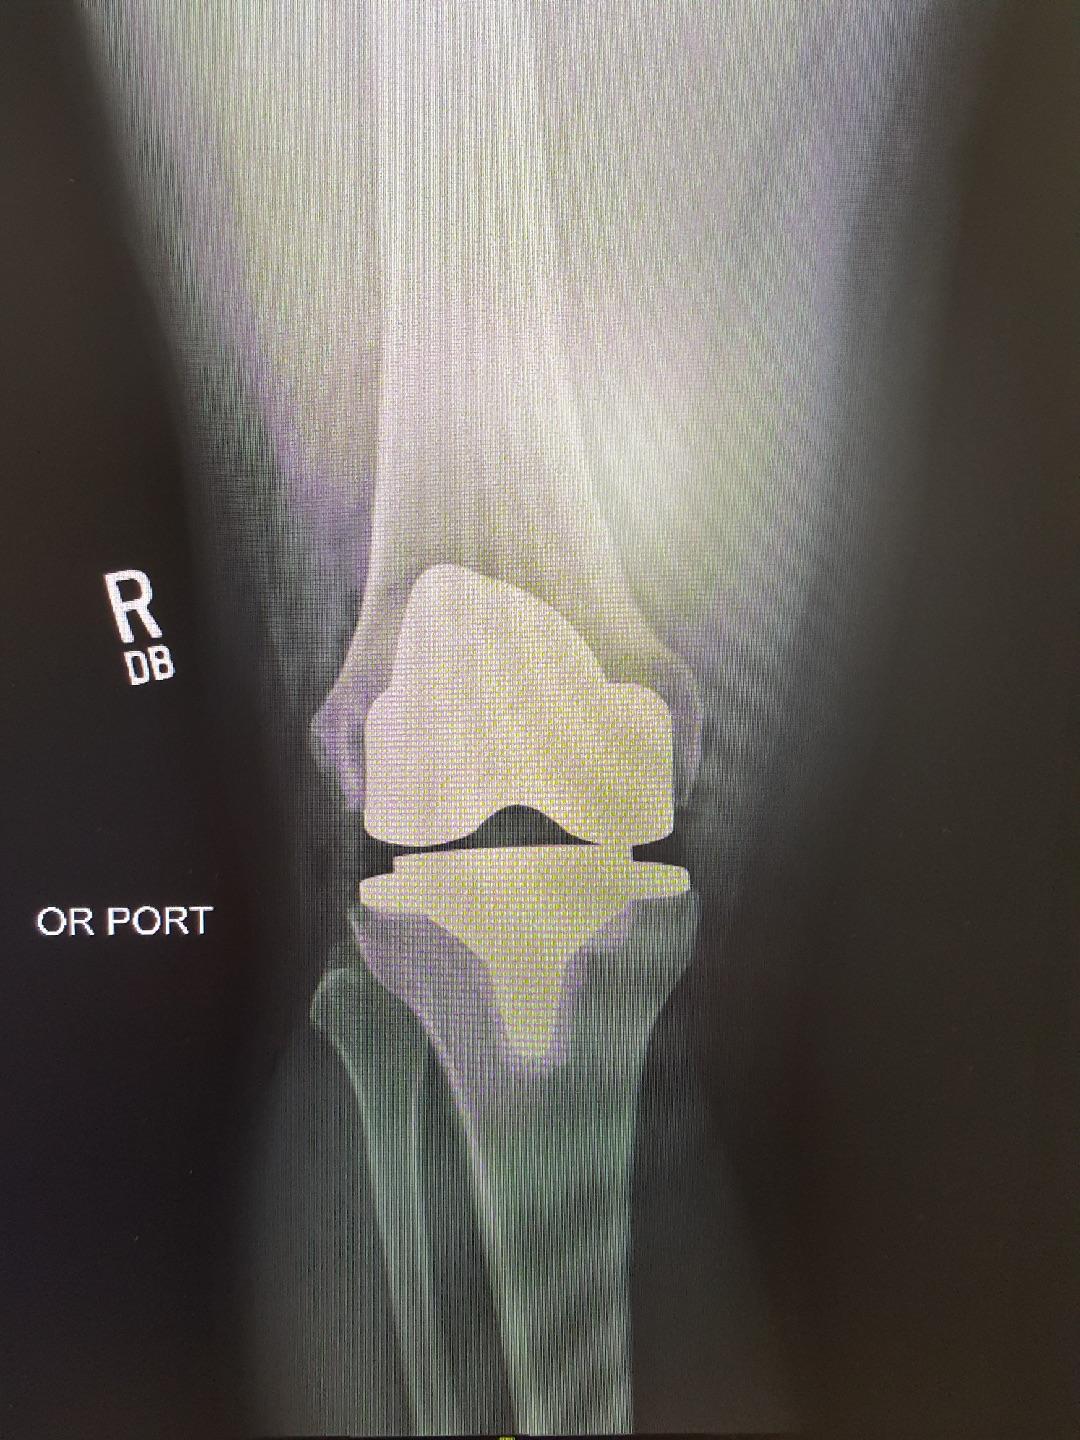

Total Knee Replacement OrthoInfo AAOS Can You Get Arthritis In Replacement Knees Joint replacement surgery can relieve the symptoms of advanced osteoarthritis of the knee very effectively in most people. If you have tried all other osteoarthritis treatment options and still have knee pain, your doctor may suggest knee replacement. You might consider a joint replacement if you have symptoms in your knee or hip such as: Osteoarthritis is the most common. Can You Get Arthritis In Replacement Knees.

Total Knee Replacement for Osteoarthritis Benefits and Cost Can You Get Arthritis In Replacement Knees Is joint replacement right for you? Joint replacement surgery can relieve the symptoms of advanced osteoarthritis of the knee very effectively in most people. This is a good option for someone. The most common symptoms are pain, swelling and. Revisions in younger patients happen twice as often as in older patients. Osteoarthritis is the most common type, and you can. Can You Get Arthritis In Replacement Knees.